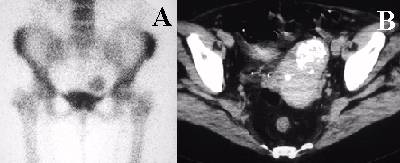

Anterior image of the pelvis from a bone scan shows increased uptake in the soft tissues above the bladder.

Uterine fibroid